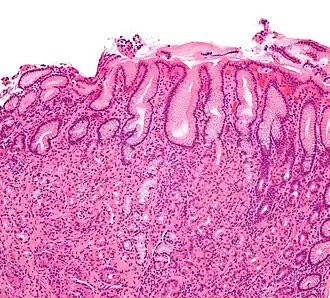

| Micrografia de gastrite. Coloração H&E. | |